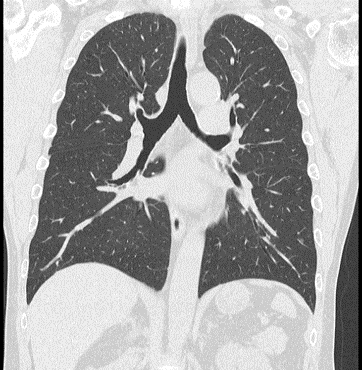

そこで、精度の高いCT検査を活用することで、より早期の肺がんを発見することができます。

■ 胸部X線検査では発見が難しい小さな肺がんも早期発見が可能

■ 肺がんのほか、肺気腫などの慢性閉塞性肺疾患を見つけることができます